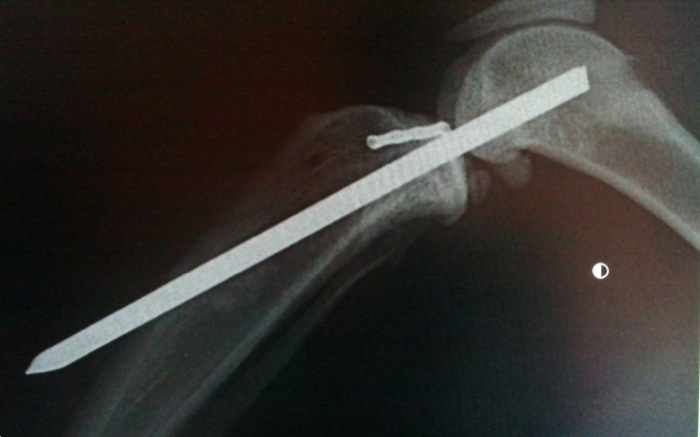

Una vez limpia la articulación de coágulos, fibrina, restos de ambos ligamentos cruzados y meniscos se implanta un clavo centrado y encima del surco rotuliano. El lugar de salida es exactamente en el origen del ligamento cruzado craneal para entrar posteriormente en la meseta tibial donde este ligamento debiera insertarse.

La artrodesis o anclaje articular temporal queda en la posición esperada en un segundo intento. Se realizó previamente una prueba con una aguja de Kirshner de pequeño calibre pero la dirección de salida no era idónea. Sí en un nuevo intento saliendo distal y por el centro de la cresta tibial.

El control habitual intraquirúrgico donde normalmente se valoran estabilidades, grados de movilidad, roces o no de los implantes, tensiones, etc. no es posible en este caso y es por ello que se tiene aún mas cuidado en conseguir una posición concreta de los implantes. No obstante recordemos que la inmovilidad articular impedirá cualquier lesión o roce en zonas de inserción del clavo.

El animal se mantuvo dentro de casa y se limitó en lo posible su movilidad sobre todo en alturas pero aparece al mes y medio de la intervención con este desplazamiento. Aunque la inmovilización de la rodilla se pensó para dos meses se decide liberar la articulación y valorar. Algunos autores recomiendan esperar entre 6 y 8 semanas.